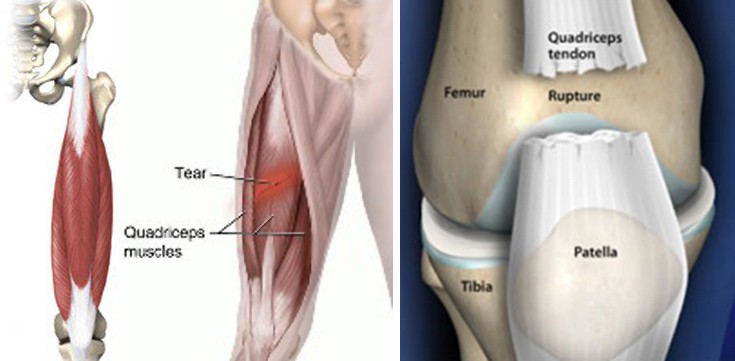

Ο τετρακέφαλος μυς είναι ο ισχυρότερος μυς του ανθρώπινου σώματος. Ξεκινά (έκφυση) από την λεκάνη και καταφύεται μέσω της επιγονατίδος στην αρχή της κνήμης, ώστε να εκτείνει το γόνατο και να επιτυγχάνει κάμψη του μηρού προς την λεκάνη. Αποτελείται από 4 μοίρες (4-κέφαλος). Τον ορθό μηριαίο, τον έσω, μέσο και έξω πλατύ.